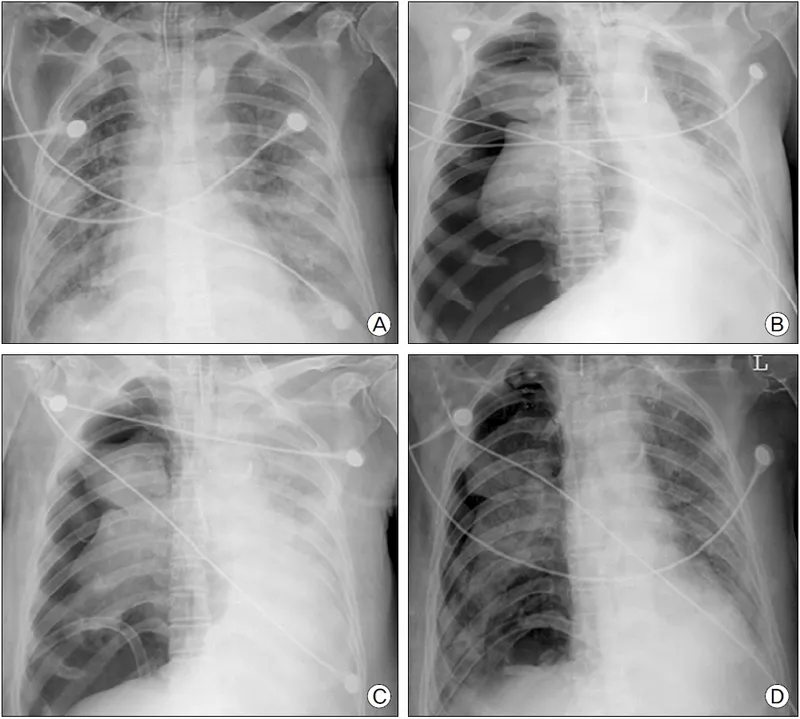

- Hypoxemic: e.g., ARDS, pneumonia ($PaO_2/FiO_2 < \textbf{200}$)

- ARDS: LPS: $V_T$ 4-6 mL/kg PBW, PEEP guided by $SpO_2$/FiO2.

⭐ In pediatric ARDS, target $P_{plat}$ ≤28-30 cmH2O; higher PEEP may be needed.